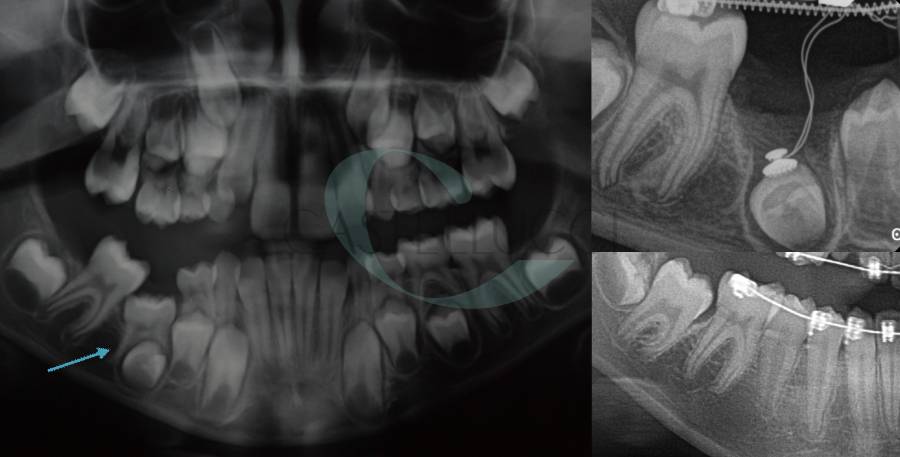

• Disinclusione chirurgica degli elementi dentari permanenti ritenuti